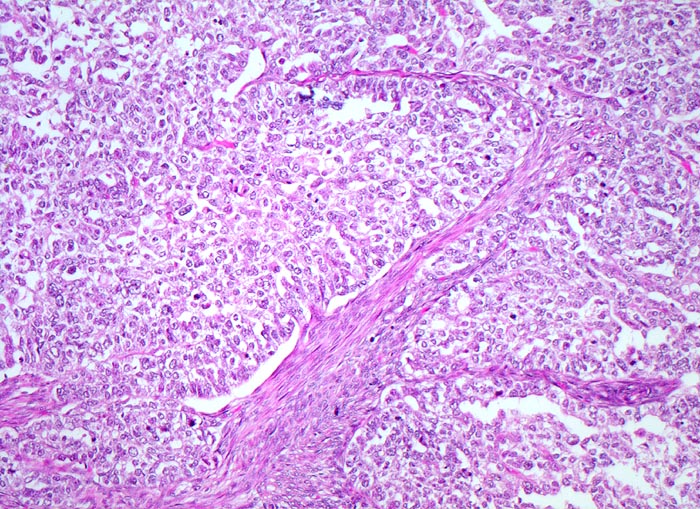

wenig differenziertes endometrioides Adenokarzinom

Vorwiegend solide zellreiche invasive Karzinomanteile. Zwischen den soliden Tumorzellplatten schmale Streifen von glatter Muskulatur des Myometriums.

Die Gradierung der endometrioiden Adenokarzinome (G1 bis G3) basiert auf dem Anteil solider Tumoranteile verglichen mit dem Anteil glandulärer Tumoranteile. Wenig differenzierte Tumoren bestehen zu über 50% aus soliden Tumorarealen. Schwere Zellatypien in einem architektonisch hochdifferenzierten Tumor mit hohem glandulärem Anteil erhöhen den Tumorgrad. Wenig differenzierte Tumoren haben eine schlechtere Prognose.